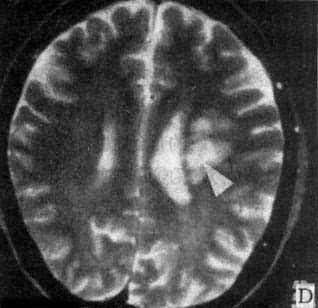

图5-1-6 MRI扫描SE序列图像 在矢状面(A)和冠状面(B)T1WI可见垂体肿块向鞍上延伸,呈等信号区(→);在横断面T1WI(C)和T2WI(D)上分别可见左枕和右基底节区脑梗塞灶呈低和高信号区(→);在矢状面T1WI(E)和横断面T2WI(F)上,可见基底动脉瘤环形影,其内为低信号和高信号区,高信号区为瘤内血栓形成(→) 七、颅内感染 颅内感染的病种很多,包括化脓性、结核性、病毒性和感染,以及脑寄生虫病。 (一)化脓性感染 化脓性脑膜炎早期CT扫描常无异常发现,脑膜粘连可出现脑室积水。并发硬膜下或外积脓时,在脑凸面或大脑镰旁可见新月形或梭形低密度灶,脓肿壁明显增强。脑脓肿早期CT表现为边缘模糊的低密度灶,伴有占位效应,代表急性脑炎期。脓肿形成期在大片低密度区内可见等密度环,壁薄和均匀性环形强化;产气杆菌感染,脓腔内可出现气泡或液面。CT可明确脓肿的部位、大小、数目和多房性;协助脓腔穿剌引流,并动态观察其发展和演变过程。目前脑脓肿的死亡率已由过去的36%~53%下降接近为零,这是由于CT的早期诊断和精确定位,配合临床及时准确治疗的结果。 (二)结核性感染 结核性脑膜炎的脑底渗出或肉芽增生,在CT上可表现为脑底池广泛或局灶性增强。结核瘤则出现等或混杂密度灶,可有钙化,均匀或环形强化。 (三)病毒性感染 单纯疱疹病毒性脑炎,CT表现为颞区低密度灶,边界模糊或清楚,占位效应轻,无增强。散发性脑炎可由多种病毒感染引起,CT上显示脑内散在性低密度灶,有时CT扫描阴性。 (四)真菌性感染 自然界普遍存在着真菌,当机体免疫或能低下时,常易罹患真菌感染,常见者有新形陷球菌、毛霉和茀状菌等。CT表现为脑炎、脑膜炎、肉芽肿、囊肿、脑出血或脑梗塞。真菌性肉芽肿呈等或高密度灶,灶周有脑水肿,增强CT呈大小和数目不等的强化结节,类似脑转移瘤的CT改变。 (五)脑寄生虫病 脑囊虫病典型CT表现为多发性小囊,囊壁或囊内的致密小点代表虫体的头节;散在性小圆形钙化点则表示死亡变性的囊肿;有时二者同时存在提示重复感染。脑血吸虫病急性脑炎型CT表现为低密度脑不肿区;慢性肉芽肿型则表现为强化结节,其形状、大小和数目不一。脑包虫病CT表现为巨大脑内囊肿,边界清楚,CT值类似水,周围无水肿。 CT扫描阴性的颅内感染性疾病例如脑膜炎和病毒性脑炎等,MRI常可获得进一步的证实。 八、其他脑疾病 (一)变性脑病 大脑变性脑病常见的老年性痴呆和多发脑梗塞性痴呆,CT扫描可见幕上脑室普遍性扩大,脑沟增宽,对称或非对称性,血管性痴呆尚可见多发性新老梗塞灶存在。 小脑和脑干变性疾病常见的有橄榄-脑桥-小脑萎缩和Marie共济失调,CT显示第四脑室扩大,小脑上沟增宽,后颅凹脑干周围脑池扩张。 基底节变性疾病有Wilson病、Parkinson病和CO中毒等,CT上显示脑室扩大以侧脑室前角扩大为明显,脑底池和外侧裂池增宽,脑基底节区有时可见对称或非对称性低密度灶。 (二)脱髓鞘脑病 先天性髓发育不良或称为脑白质营养不良,可见于异染性脑白质营养不良、类球状细胞白质营养不良、肾上腺脑白质营养不良等。CT表现脑白质对称性密度减低,与脑皮质的对比鲜明。获得性髓鞘脱失又称为脑白质病,常见有多发性硬化和皮质下小动脉硬化性脑病等,CT表现为脑室周围散在性斑片或带状低密度灶,伴有程度不同的脑萎缩。 (三)先天性畸形 脑膜(脑)膨出CT可见颅骨缺损,自缺损处突出一液性软组织包块,有的包块内有脑组织。胼低体发育不全显示双侧侧脑室扩大并分离,第三脑室扩大向上前移位于分离侧脑室之间,有的合并脂肪瘤或囊肿。Chiari畸形上CT可见小脑扁桃体下疝;有时伴有脑干、小脑和第四脑室延长下疝及脑积水改变,可合并脊髓空洞症、脑膜膨出及其他脑脊髓畸形。 (四)新生儿脑病 新生儿窒息CT可见弥漫性脑水肿、颅内出血或脑室内外积水。新生儿颅内出血由于产伤或缺氧所引起,出血于硬膜下或硬膜外腔、蛛网膜下腔、脑和脑室内,而以室管膜下出血具有特征性,CT表现沿脑室壁出现高密度线形影,后期遗留交通或非交通性脑积水。 MRI对许多变性脑病、脱髓鞘脑病和先天性畸形能够比CT提供更多的信息资料,可作为CT扫描诊断的补充。 九、脊柱和脊髓疾病 (一)椎管狭窄 椎管狭窄分为骨性和软组织狭窄,骨性椎管狭窄又分为中心型狭窄和周围型狭窄,后者指侧隐窝和椎间孔狭窄。先天性椎管狭窄常伴发于骨发育不全;获得性椎管狭窄可由骨折、炎症、肿瘤和退行性变引起,临床上出现一系列脊髓、脊神经和营养血管的压迫症状。横断面CT扫描可直接观察椎管狭窄变形,测量椎管大小并探明引起椎管狭窄的病因。 (二)椎间盘脱出CT扫描可直接显示突出于椎管或椎间孔内的软组织块影,与椎间盘相连或游离于椎管内,硬膜囊受压变形,硬膜外脂肪层变薄或消失,脊神经根增粗或湮没。椎间盘性变性显示变扁变形,向周围膨出,或出现气体(直空现象)。MRI上显示更为清楚。 (三)脊髓疾病 脊髓损伤急性期可见脊髓出血、水肿、受压、移位、挫伤或断裂;慢性期可见脊髓软化、萎缩、囊变或空腔化。脊髓肿瘤位于髓内者多为星形细胞或室管膜瘤,髓外硬膜内者多为脊膜或神经纤维瘤,硬外肿瘤以转移瘤常见。脊髓造影配合CT扫描才能对椎管内肿瘤作出正确的定位诊断。先天性畸形常见有脊髓空洞症、脊髓纵裂和脊髓血管畸形等,后者需行增强CT扫描。可显示脊髓表面扩张扭曲的血管影,并能确定血管畸形在椎管内大致伸延的范围。 MRI的软组织分辨率比CT高,矢状面扫描图像上可直观地显示脊髓病变的全貌及与周围组织结构的关系,是当今诊断脊髓疾病的最佳选择。 (责任编辑:泉水) |